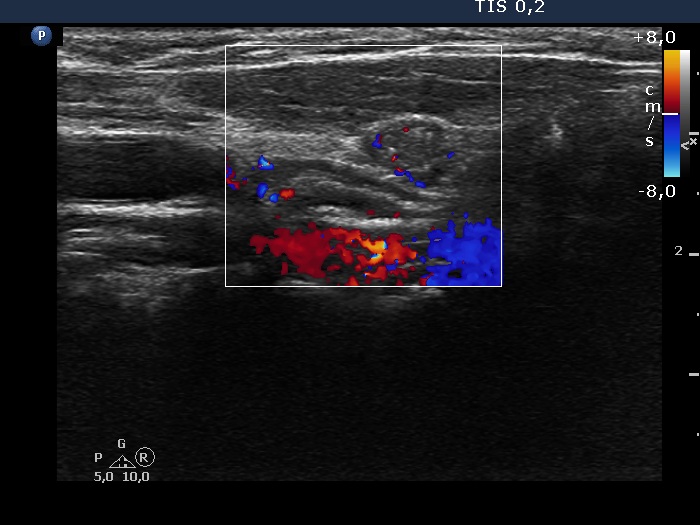

Left lobe, longitudinal view, color Doppler mode. The lesion shows vascularity in this image.